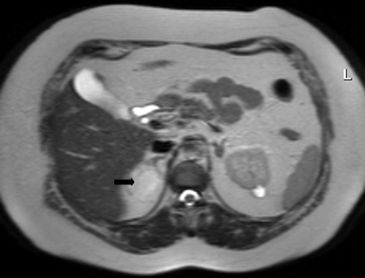

Figura 3. Glándula suprarrenal normal en resonancia magnética. (a) Cortes axial ponderado en T1 la señal de la glándula normal (flecha negra) es hipointensa respecto a la grasa retroperitoneal e isointensa respecto al parénquima hepático. (b) Cortes axial ponderado en T2 en que se muestra la glándula suprarrenal derecha (flecha blanca) y (c) corte coronal ponderado en T2 en que se muestra la glándula suprarrenal derecha (flecha blanca) y la glándula suprarrenal izquierda (flecha negra) con similares características de intendidad de señal. 3. Causas y prevalencia de las lesiones suprarrenales